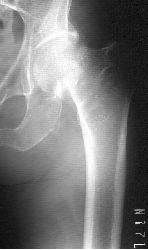

◆脚の付け根 大腿骨近位部骨折(転子部骨折・頸部骨折)

脊椎圧迫骨折 橈骨遠位端骨折 大腿骨転子部骨折 大腿骨頸部骨折 上腕骨近位部骨折

■日本における高齢者寝たきり患者の原因疾患は、脳血管疾患に

次いで、骨粗鬆症・骨折が第2位です。特に大腿骨近位部骨折は

寝たきりの原因になりやすく注意が必要です。2014年には、年間

約20万人の大腿骨近位部骨折が発生しており、今後更に増加すると

考えられています。